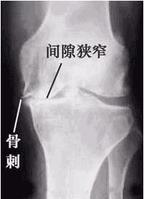

X线平片不仅仍为本病的常规检查方法,有的学者还认为它是追踪病情变化的金标准。拍膝关节片时,病人应取站立位拍前后位和侧位片,髋关节和手关节可只拍前后位片。在早期阶段,X线片大多正常,中晚期可见关节间隙不对称性狭窄、关节面下骨硬化和变形、关节边缘骨赘形成,关节面下囊肿和关节腔游离液体等。骨性关节炎的x线特点为:①关节间隙狭窄,如在膝关节,可小于3毫米;②关节面硬化变形;③关节边缘骨赘;④关节鼠;⑤软骨下囊性变,其边缘分界清楚;⑥骨变形或关节半脱位。

X线片可分为五级。0级:无改变;1级:轻微骨赘 2级:明显骨赘,关节间隙正常;3级:骨赘外关节间隙中度狭窄;4级:骨赘外关节间隙严重狭窄,伴软骨下骨硬化。